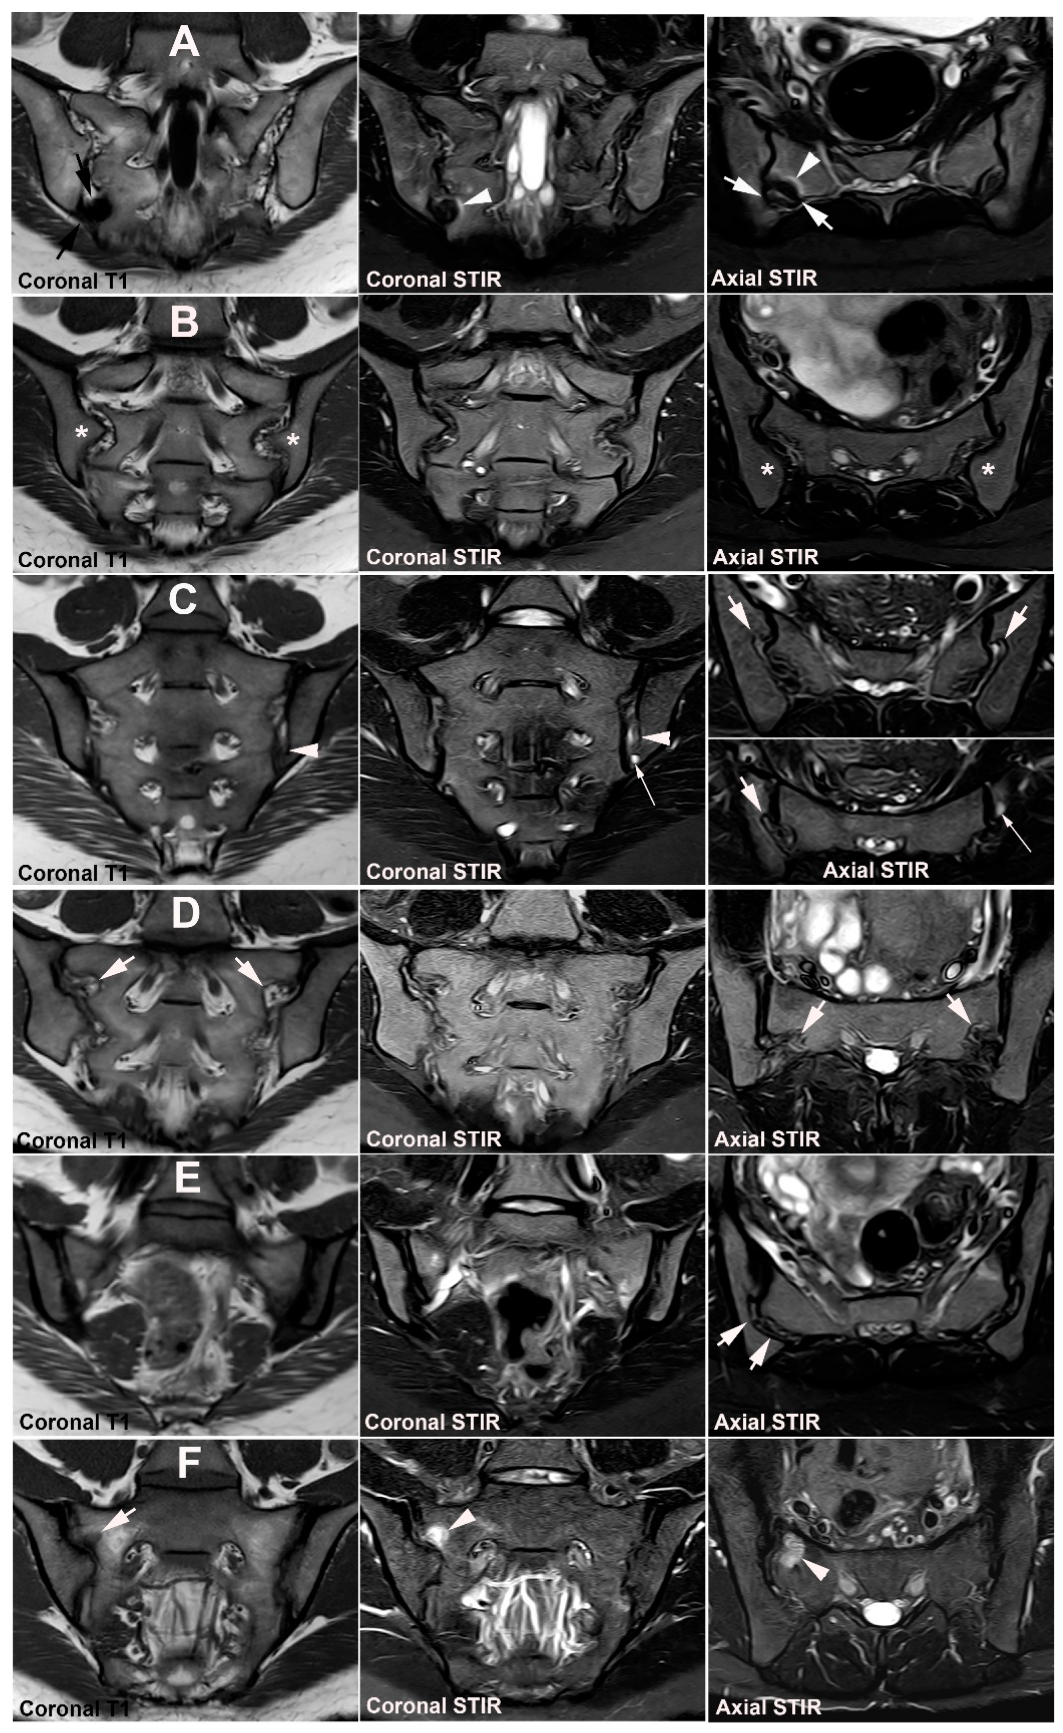

4. Anatomical Variations

4.1. Well Described SIJ Variants

4.2. Persistence of Unfused Nuclei in Adulthood

4.3. Lumbosacral Transitional Vertebrae

5. Osteitis Condensans ilii and Pregnancy-Related Changes

5.1. Osteitis Condensans ilii (OCI)

5.2. Pregnancy-Related Changes

6. Other Strain-Related SIJ Changes